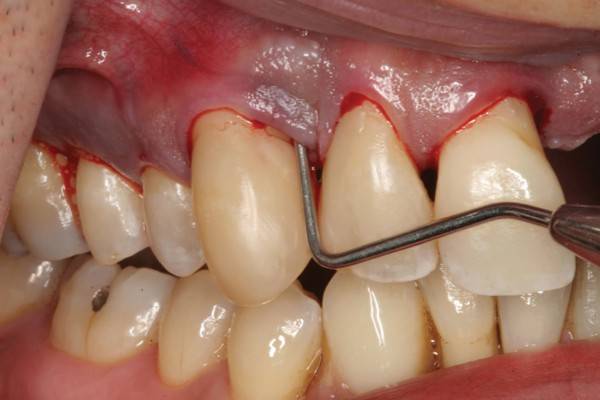

Ở thời gian đầu, bệnh nhân chỉ có các biểu hiện cao răng đóng ở cổ răng, nướu sưng to, dễ chảy máu khi đánh răng nên mọi người càng ngại đánh răng khiến tình trạng viêm nướu càng trầm trọng.

Nếu điều trị ngay từ giai đoạn này rất đơn giản và mang lại hiệu quả cao. Còn khi đến giai đoạn nướu tự chảy máu, không động vào vẫn có hiện tượng chảy máu thêm hơi thở hôi, thậm chí có chảy mủ ở nướu răng, ăn nhai kém, răng lung lay… việc điều trị trở nên phức tạp và tốn kém nhưng kết quả mang lại không được hoàn hảo như ban đầu.

"Súc miệng nước muối, lấy cao răng, hay uống kháng sinh chỉ làm giảm nhẹ được triệu chứng thời điểm nhất định. Còn theo đúng tiêu chuẩn, bệnh nhân sẽ cần nạo nha chu, phẫu thuật nha chu với mục đích làm sạch dứt điểm", BS Anh Ngọc nói.